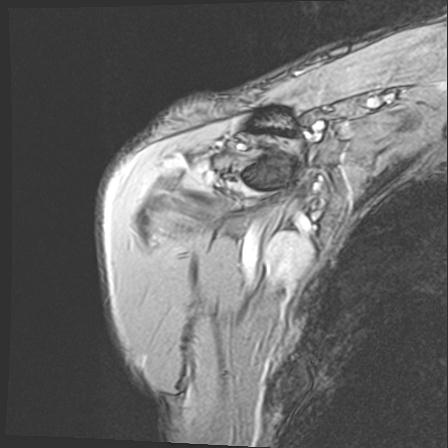

60058 3/9 11/4 右肩 2R+MRI 73歳男性 肩腱板損傷